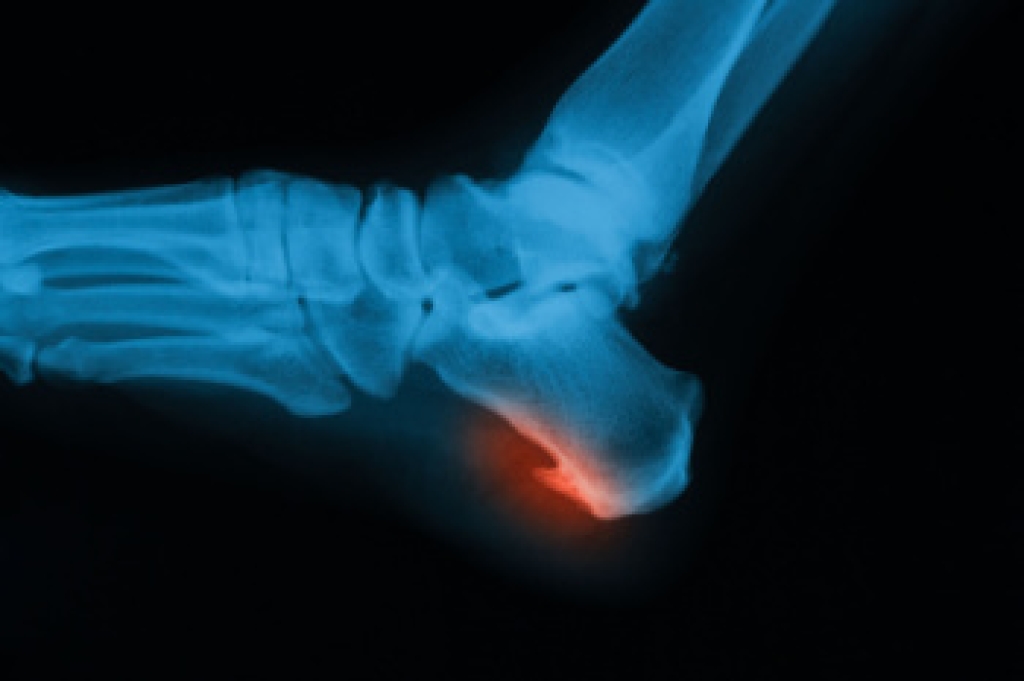

Heel pain is often associated with plantar fasciitis. The plantar fascia is a band of tissues that extends along the bottom of the foot. A rip or tear in this ligament can cause inflammation of the tissue.

Heel spurs are another cause of pain. When the tissues of the plantar fascia undergo a great deal of stress, it can lead to ligament separation from the heel bone, causing heel spurs.